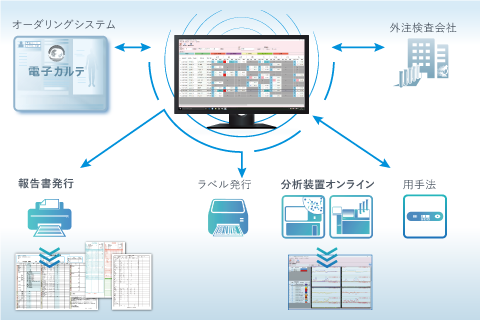

画像ファインリングシステム PACS 放射線情報管理システム

放射線情報管理システム レポートシステム

レポートシステム 検査システム

検査システム 健診システム